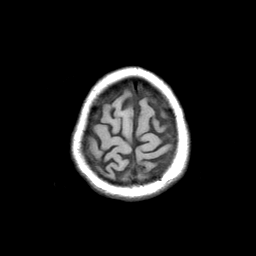

Basal Ganglia Calcification: T1-weighted MR -- Slice #16

[Home][Help][Clinical] Slice 16